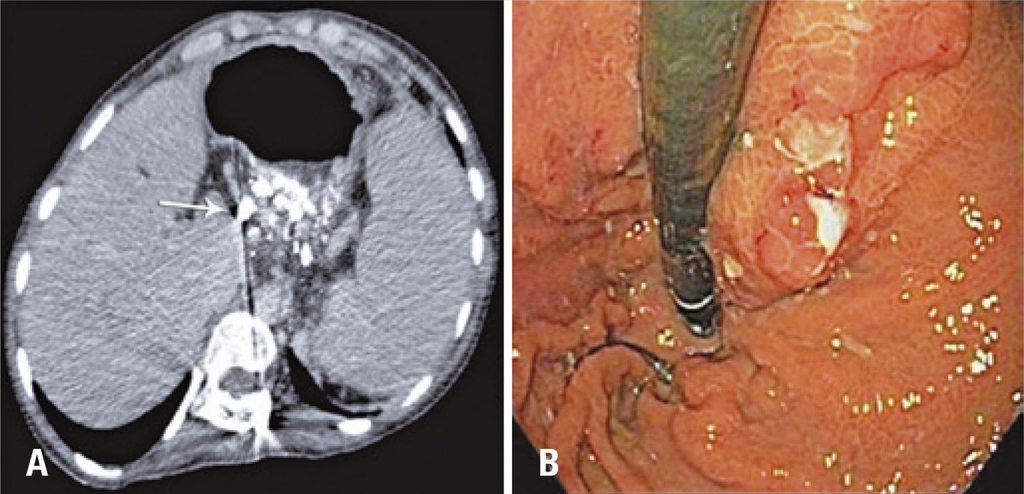

Figure 4

Control exam after 30 days. (AG) Computed tomography after 30 days showing gastric varices filled with fluid agent (Onix®), white arrow. (B) Upper digestive endoscopy of control 30 days after the procedure